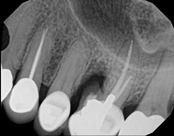

Non-surgical root canal treatment:

Before

Immediately After

6-month follow-upThis patient presented with pain when chewing. Diagnostic testing was done and determined it was the lower molar. The diagnosis was: pulpal necrosis, symptomatic periradicular periodontitis. Root canal treatment was performed with laser disinfection. The tooth had a crown and we accessed the tooth through the crown. We saved the tooth and the crown.